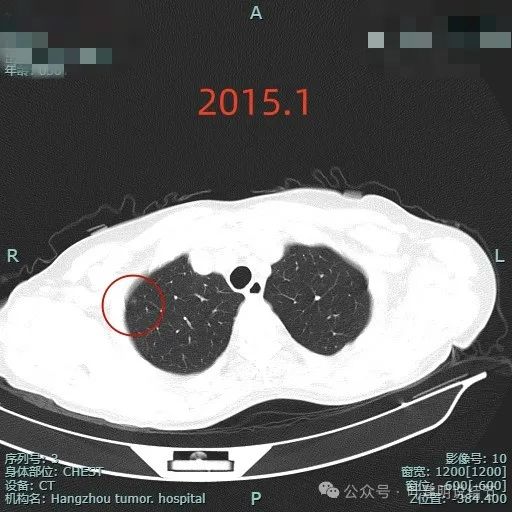

回头看2015年此处就有异常,是微小的纯磨玻璃结节,边缘似乎稍模糊,不是典型恶性范畴结节的影像表现,至少肯定是能先随访的。